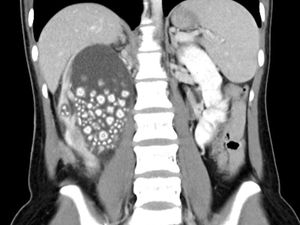

Batu ginjal merupakan endapan keras yang terbuat dari mineral dan garam yang terbentuk di saluran kemih. Ternyata ada 5 kebiasaan yang bisa memicunya terjadi.